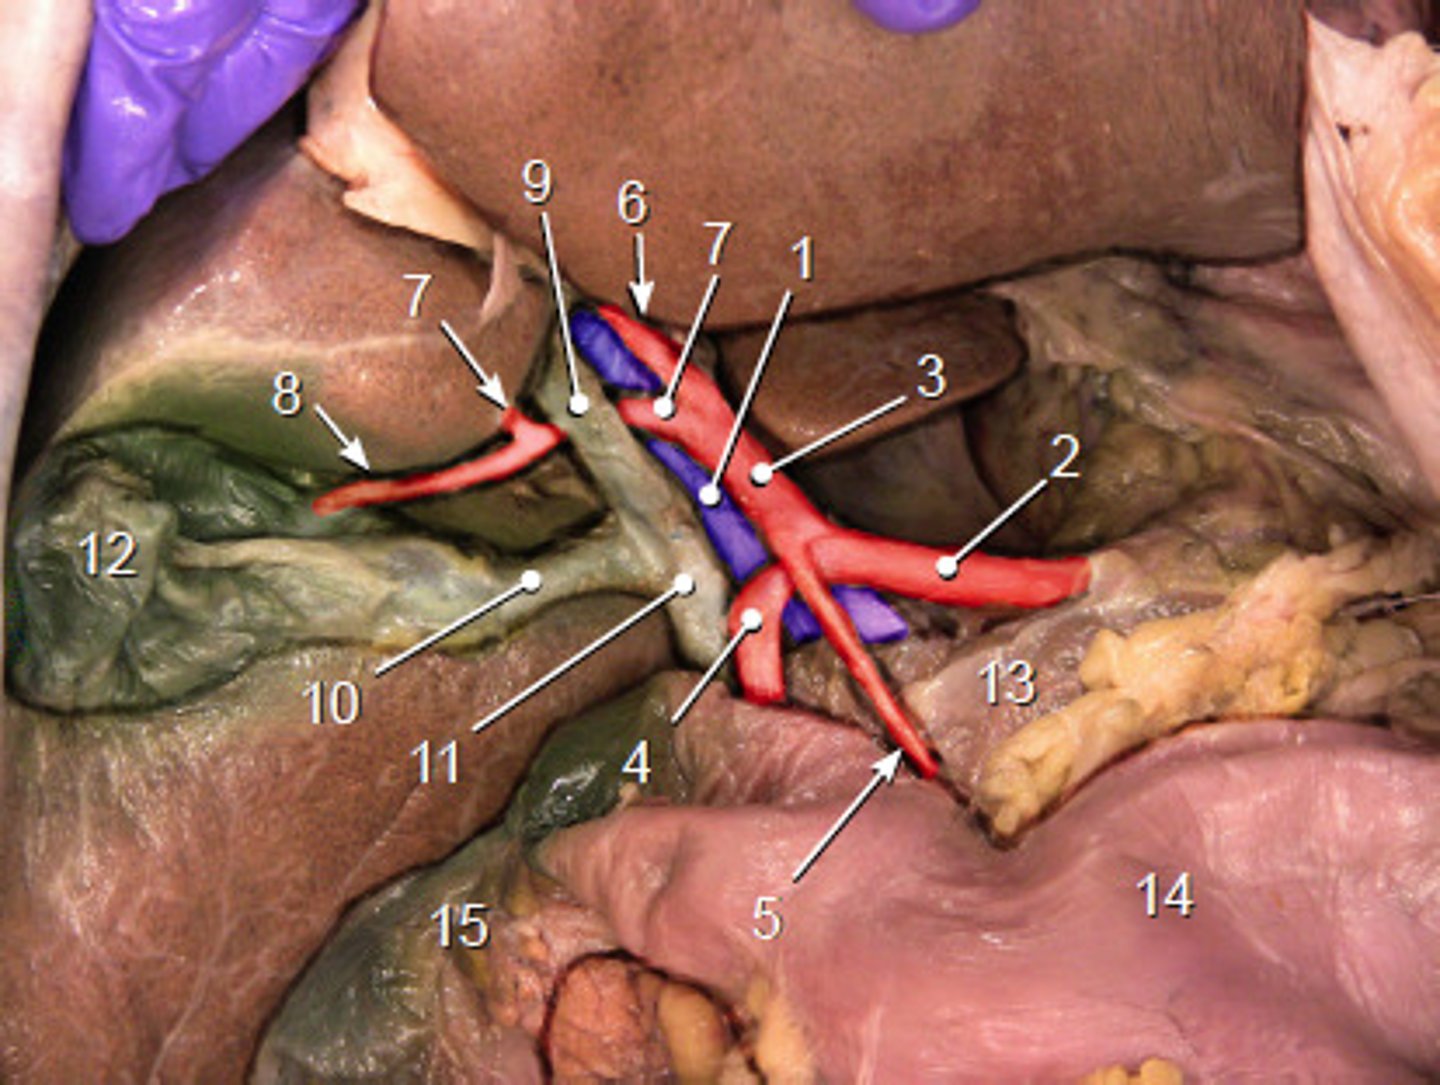

portal triad

what is in this structure

porta hepatis

where the blood and lymph vessels, bile ducts, and nerves enter and leave the liver

hepatic artery proper

3

right hepatic artery

left hepatic artery

cystic artery

8

common bile duct

common hepatic duct

cystic duct

hepatic portal vein